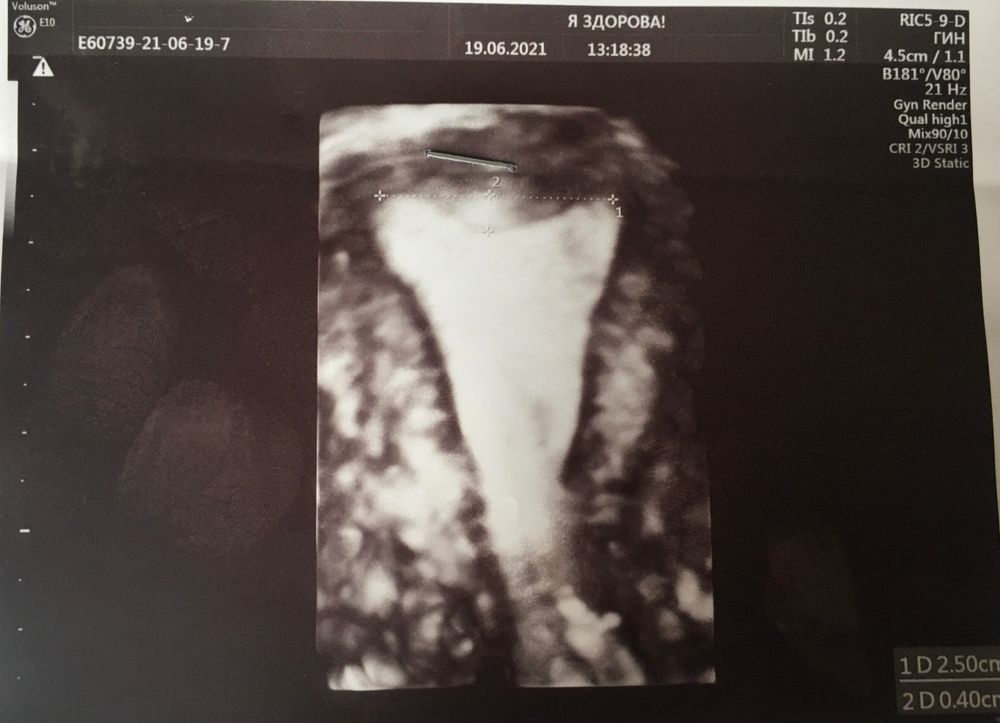

Девочки, привет! Рассказываю про вчерашний приём у Тетруашвили. Зашла я в клинику в 8:30, на приём зашла к 17 часам 😀. На первый взгляд казалось народу не много, человек 15, но потом начали появляться народ по времени, все смешалось и вышла вот такая очередь. Благо было где присесть, одна женщина в конце просто легла спать растянувшись на стульях и укрывшись. Вообщем, медсестра записала с моих слов мою историю, пришла доктор, она ей все пересказала. Анализы по крови (по рекомендации) каплиной, те что на 28.000) смотрела бегло, сразу сказала, что у нас теперь маточный фактор и фактор мужской, как прежде (у мужа генетическая поломка). Спросила какой формы у меня матка «я сказала, что врачи говорят обычная с тенденцией к седловидности». Она сказала, что не седловидная, а какая то деформированная. Фотку приложу. Зацените.